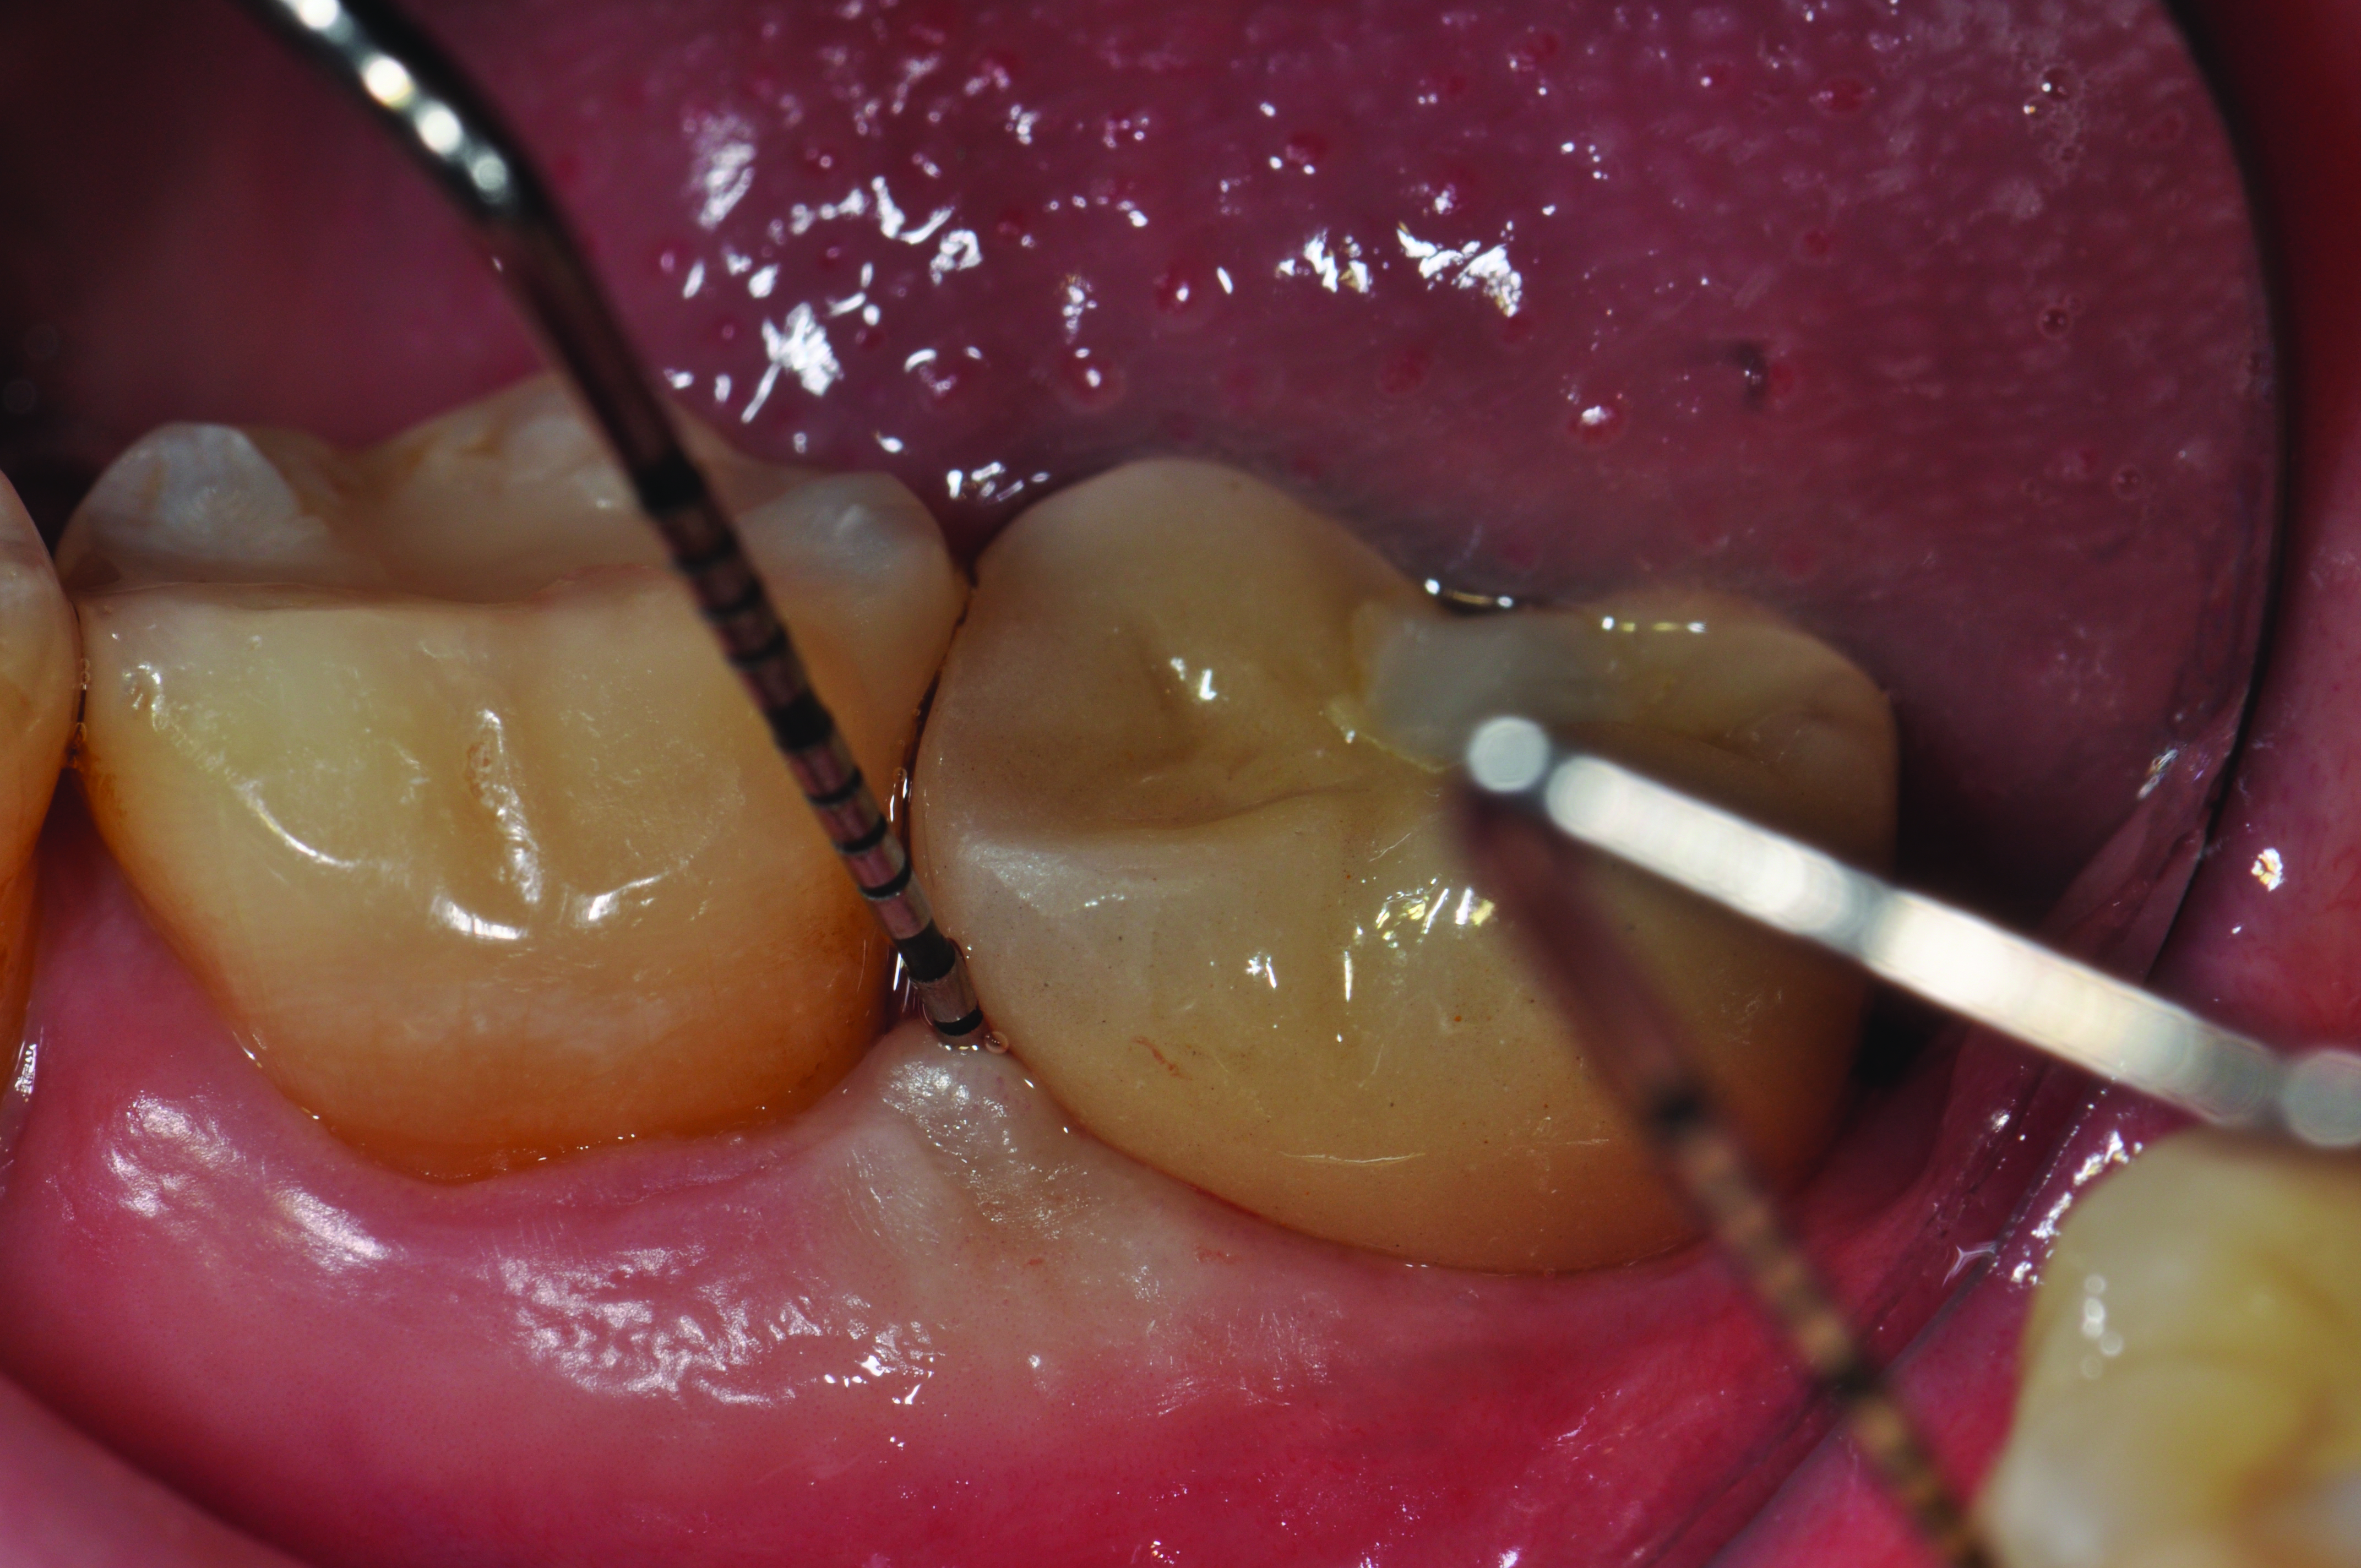

Radiograph of a mandibular left first molar implant in a 61-year-old man taken 2 years after the implant’s placement. No bone loss beyond physiologic remodeling has occurred.

Figure 5

Clinical view of this area suggests that peri-implant mucositis is present, as there is bleeding on light probing and inflammation of the tissue.

Figure 6

Four weeks following nonsurgical treatment, the area is healthy as probing depths are now shallow and bleeding is absent. Treatment involved scaling of the area, which removed all plaque and a slight amount of cement, and irrigation with an anti-inflammatory hydrogel.

Figure 7